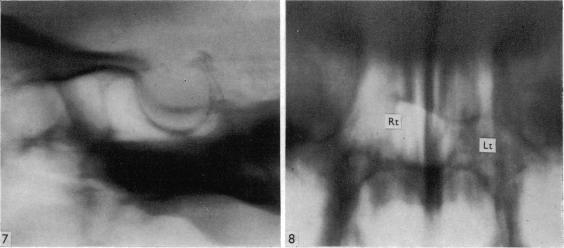

Surgical aspects of the anatomy of the sphenoidal sinuses and the sella turcica.

J Anat. 1977 Dec;124(Pt 3):541-53.